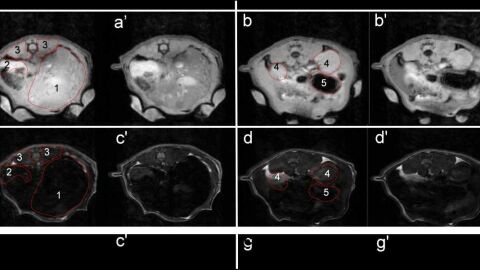

Los resultados obtenidos en animales permiten apreciar claramente que tras la administración intravenosa de este nuevo agente de contraste se produce una mejora significativa del contraste positivo y negativo en los tejidos donde se acumulan las nanopartículas.

Las pruebas de laboratorio realizada con animales apuntan a una mejora variable en función del tejido, que puede alcanzar hasta un 78% de la intensidad de la señal en las imágenes de resonancia magnética, facilitando el diagnóstico clínico.